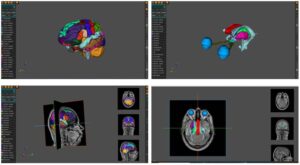

AnaVu bridges these gaps by offering students a 3D, interactive, and immersive learning experience. Its visualizations are constructed from real-world MRI and CT scan data, anonymized to ensure patient privacy, and rendered into highly accurate models of the human body. Students can explore anatomy layer by layer, rotate structures, and zoom into details that would otherwise be hard to observe in cadavers or textbooks.

A unique capability of AnaVu is its ability to visualize intricate anatomical details such as fibre tracts that otherwise require advanced, time-consuming cadaver dissection techniques which is not practical in teaching large classes. This makes it especially valuable for teaching complex anatomy concepts.